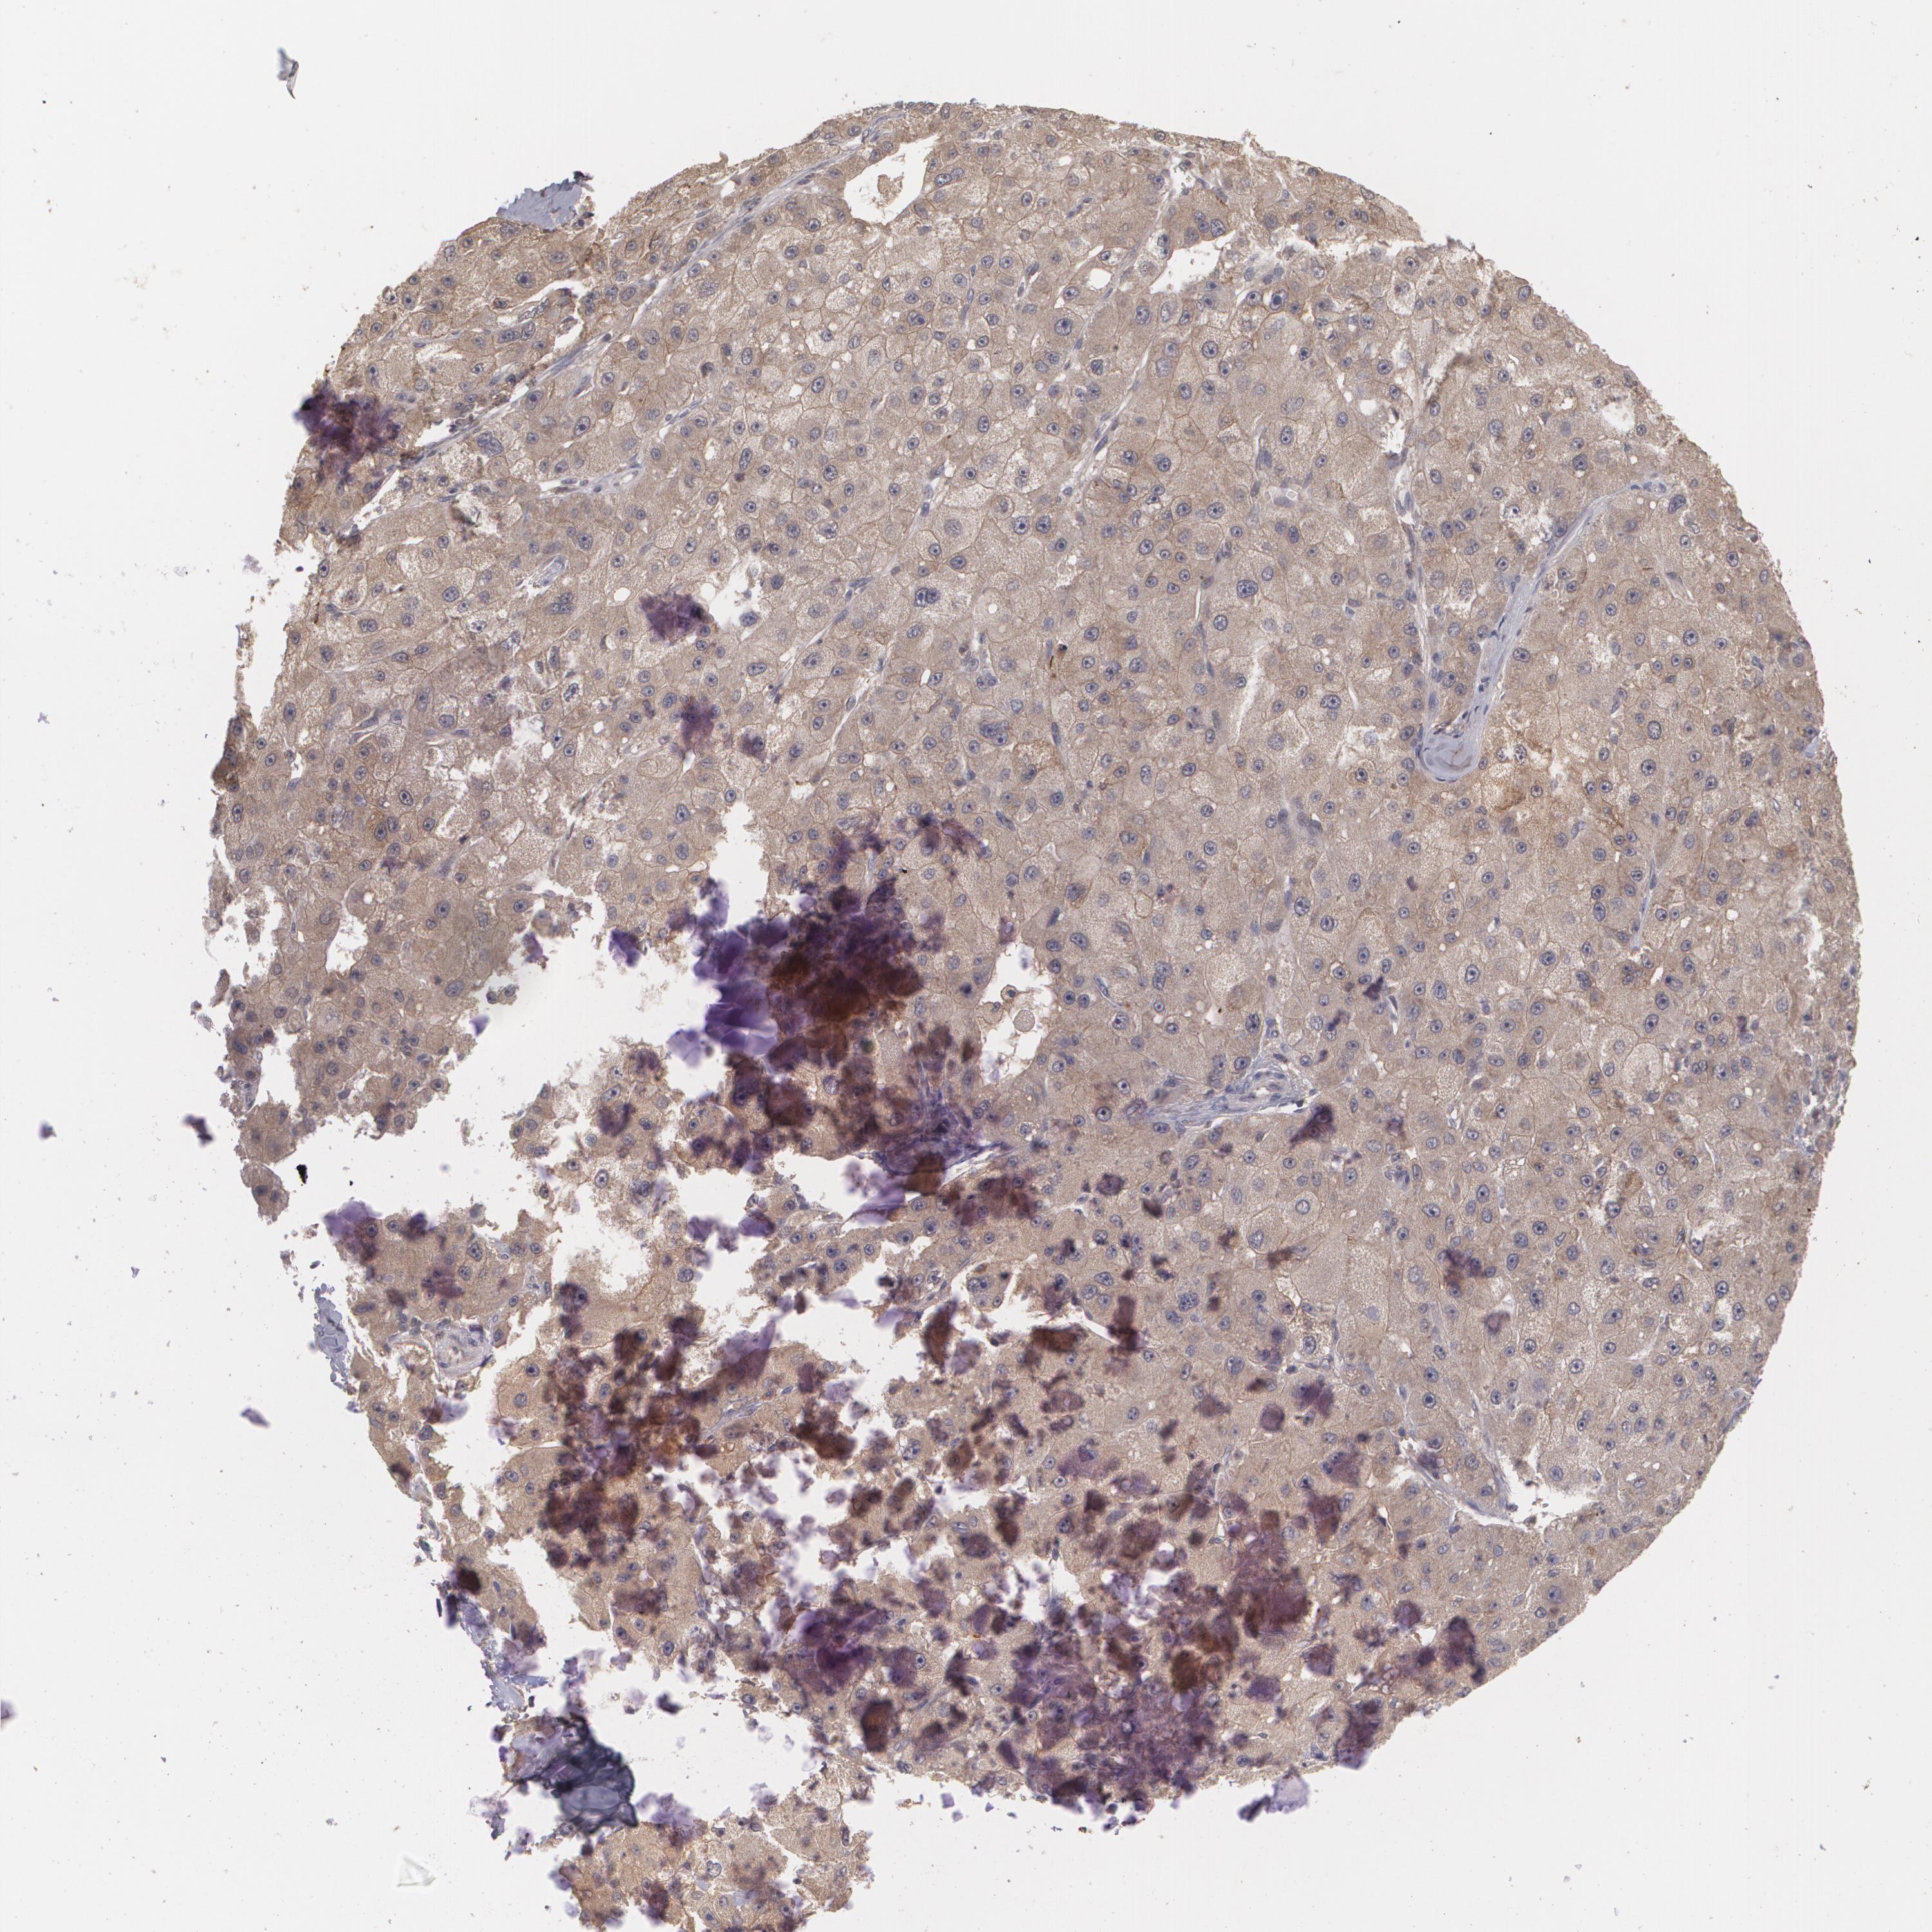

LIVER CANCER - Protein expressioni

A mouse-over function shows sample information and annotation data. Click on an image to view it in a full screen mode. Samples can be filtered based on level of antibody staining by selecting one or several of the following categories: high, medium, low and not detected. The assay and annotation is described here.

Note that samples used for immunohistochemistry by the Human Protein Atlas do not correspond to samples in the TCGA dataset.

Antibody stainingi

Antibody staining in the annotated cell types in the current human tissue is reported as not detected, low, medium, or high, based on conventional immunohistochemistry profiling in selected tissues. This score is based on the combination of the staining intensity and fraction of stained cells.

Each image is clickable and will lead to virtual microscopy that enables deeper exploration of all samples and also displays staining intensity scores, fraction scores and subcellular localization as well as patient and tissue information for each sample.

Antibody CAB002778

Staining

High

Medium

Low

Not detected

Intensity

Strong

Moderate

Weak

Negative

Quantity

>75%

75%-25%

<25%

None

Location

Nuclear

Cytoplasmic/membranous

Cytoplasmic/membranous,nuclear

Cholangiocarcinoma

Carcinoma, Hepatocellular, NOS